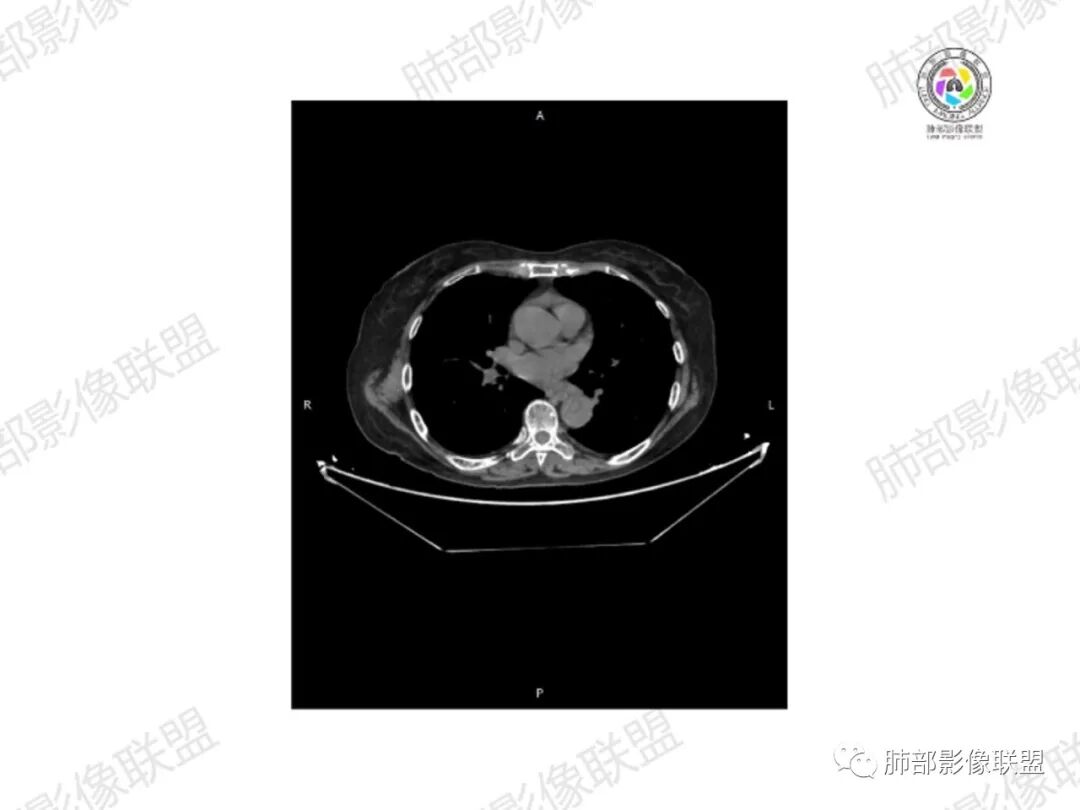

2.右髂骨轻度变形伴广泛骨质吸收破坏,边界不清且突破骨皮质。近中线区以溶骨性破坏为主,髂骨翼一侧则成骨性改变明显,骨表面见垂直骨针或花边样高密度瘤骨。

3.患骨多处皮质断裂,符合病理性骨折。注意折端可能会形成骨痂,但本例无论是形态还是部位都不符合骨痂。

4.患骨两旁(即盆骨内外)见边界不清的较大范围软组织快影,其间偶见骨化影。

1.边界不清的骨质吸收破坏,溶骨明显,骨皮质突破,软组织肿块,种种迹象表明其恶性无疑!

2.但注意这是有“成骨”的恶性骨肿瘤!我们知道老年患者的骨原发性恶性肿瘤“成骨”非常少见。少数转移瘤可为成骨型或混合型,女性患者如乳腺癌骨转移等。在男性,最典型的成骨转移是前列腺癌。

本例右侧髂骨具有较为典型的“骨肉瘤”影像学特征,有边界不清的吸收破坏、有新生骨、形成软组织肿块等等。

4.“成骨肉瘤”绝大多数发生于青少年,发生于老年患者则往往见于其他因素,如诱发于畸形性骨炎(Paget病,本例影像不支持),骨照射、骨坏死等。其他如骨旁骨肉瘤等,发病年龄可以偏大。